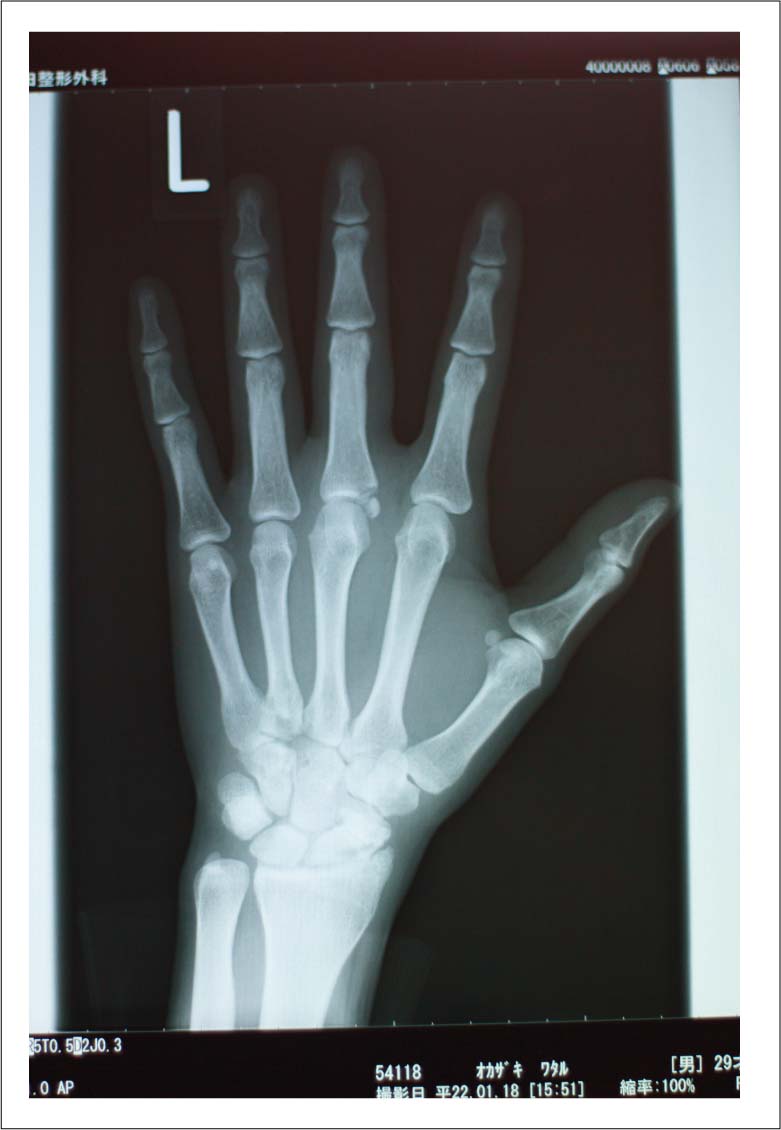

病院へ行ったら、入院前の検査だけして終わってもうた。。。

入院&手術は、来週になりました。

あと、先生がレントゲンをよく見てみると。。。手首も折れてるね〜と言われました。。ヒビみたいのが1センチほど。。。。。